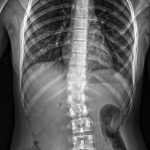

Amplio espectro de estudios

Además del tomógrafo dental, que realiza panorámicas dentales y tomografías, y permite realizar laminografías de la articulación temporomandibular (ATM) y placas de macizo facial para casos como fracturas, el servicio también ofrece estudios especializados como espinogramas y mediciones de miembro inferior con el equipo Pimax. Estos estudios de alta calidad son muy requeridos por traumatólogos de la ciudad y zonas aledañas. La calidad de imagen es tal que, según el Lic. Quiroga, pacientes de ciudades vecinas viajan a Mercedes para ser atendidos.